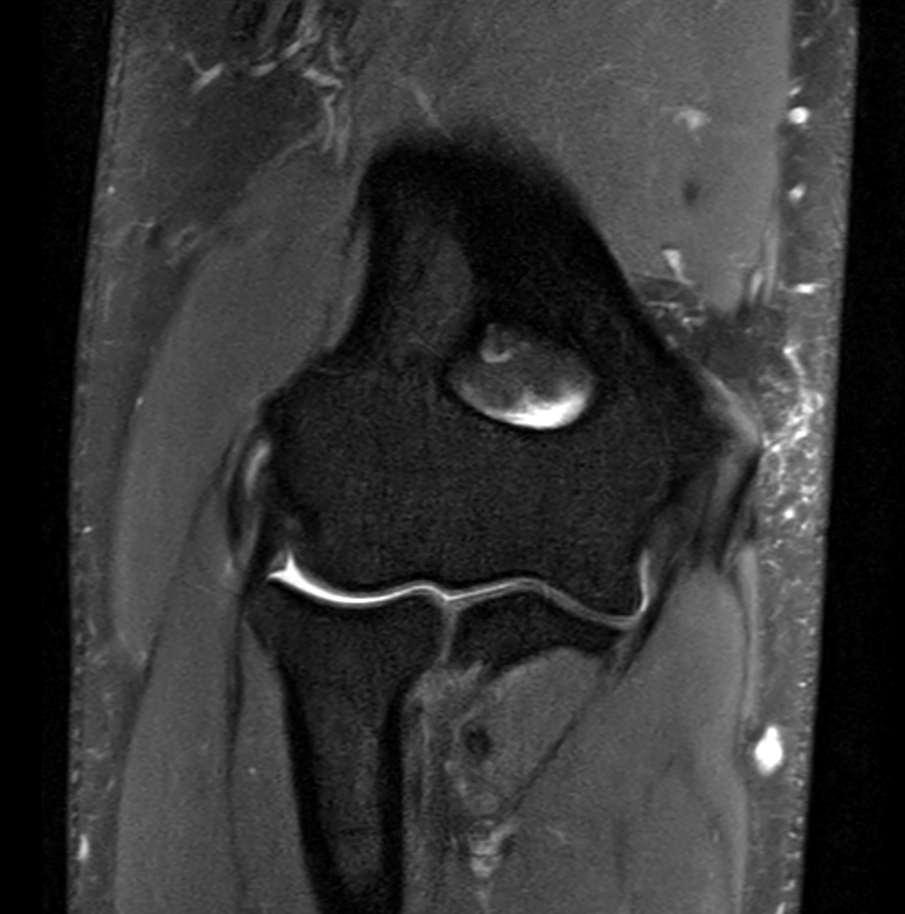

Coronal PDw SPAIR